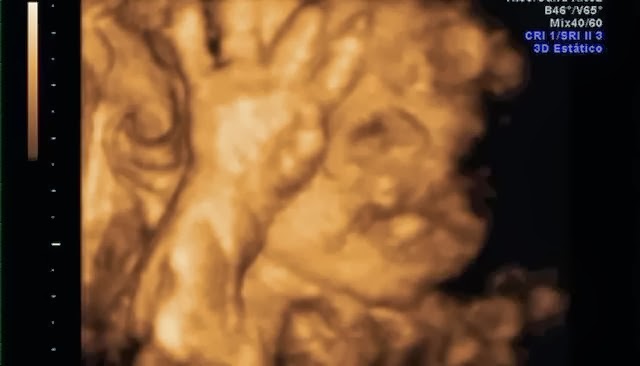

Su carita!Y estas son algunas capturas de pantalla de la eco 4d que me hice a principios de mes. Que ya de paso decir, que esta no me gustó NADA!! Tuvimos que esperar 2 horas para que nos cogieran, la eco nos la hicieron con prisas, y sólo se le vió la mitad de la cara.. así que para habernos gastado 100€ muy mal!! No os recomiendo la Ginecóloga de Gandia, Dra.Escrivá.

De momento parece que se parece a mami... jiji. Mi nariz, mi boca y mis mofletes :DEl padre se preguntó si era suyo.. jajaja, aunque tiene sus manazas.Y ahora os dejo unas fotitos de mi barriga en la playa, que aprovechando que esta semana aquí ha hecho muy buen tiempo nos hemos ido a hacernos un reportaje de fotos.